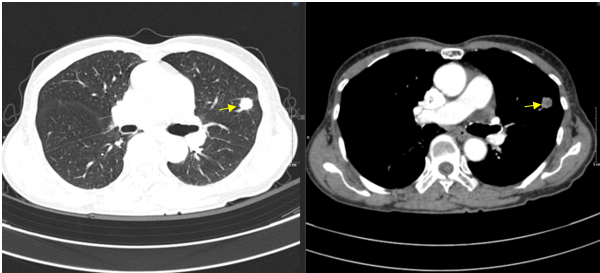

- Chụp CT lồng ngực: Nhu mô phổi hai bên rải rác vài nốt đặc, nốt lớn thuỳ trên phổi trái, kích thước 10x11mm - Theo dõi thứ phát.

Hình 2. Hình chụp CT ngực có nốt đặc thùy trên phổi trái kích thước 10x11mm.